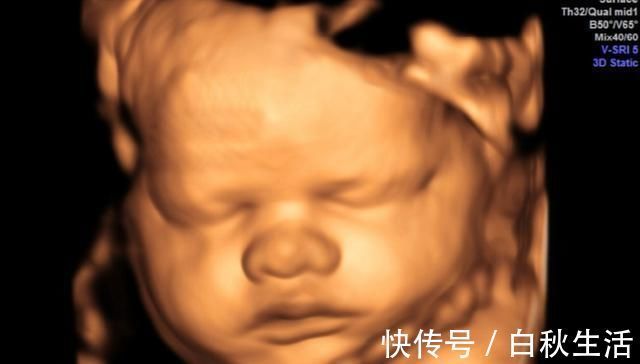

怀孕期间最重要的一项检查是大排畸检查,可以做三维彩超也可以做四维彩超。排畸检查都是绕不过去的检查,因为太重要了。

排畸检查可以查到胎儿的头面部、大脑、内脏器官、四肢、脊柱等外观是否正常,如果孩子有异常问题,需要孕妈妈们早做准备,别等到生下来再发现,到时候会给家庭带来精神和经济负担。